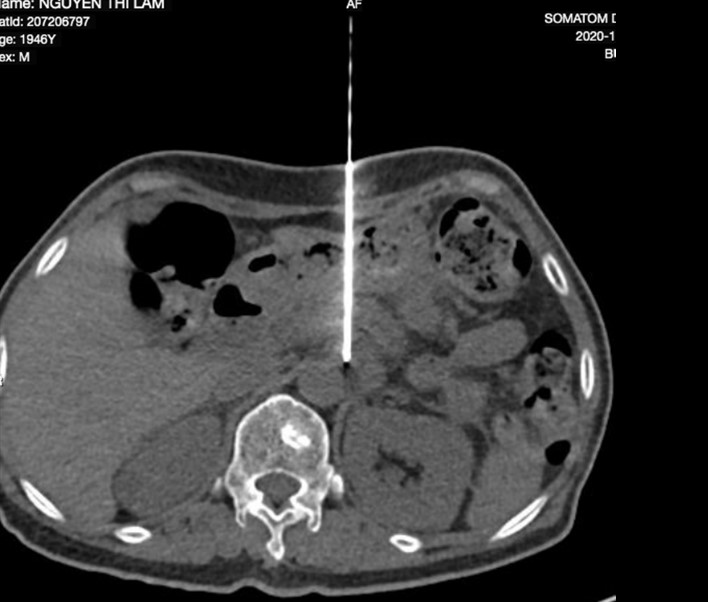

Chọc kim vào cạnh gốc ĐM thân tạng